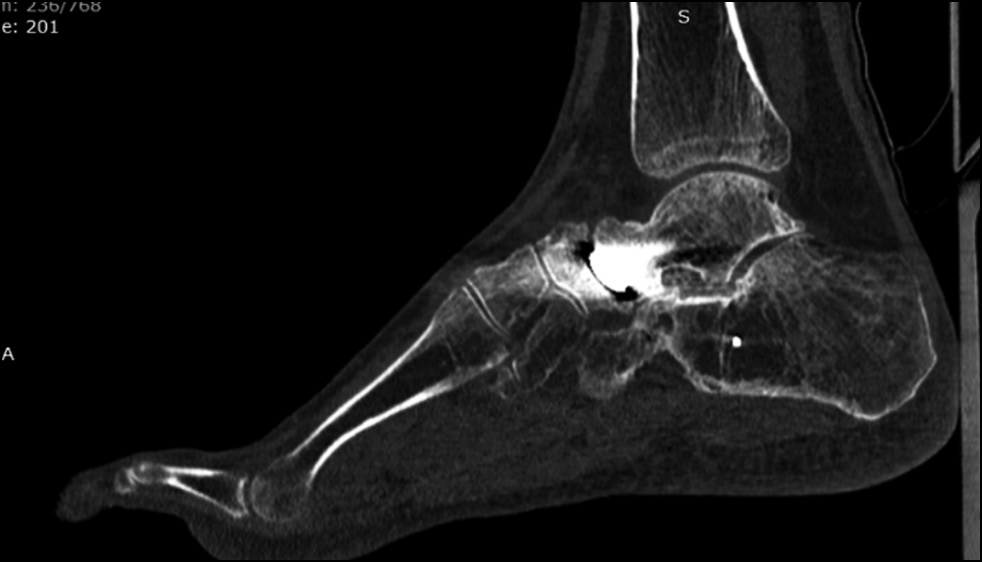

По данным компьютерной томографии выявлены грубая деформация суставных поверхностей таранно-ладьевидного сустава, аваскулярные кисты в головке таранной кости (рис. 2).

Рис. 2. Мультиспиральная компьютерная томография срезов стопы: а — сагиттальная плоскость, b — аксиальная плоскость. Определяются грубые дегенеративные изменения, выраженное сужение суставной щели таранно-ладьевидного сустава. В головке таранной кости определяется киста.

Fig. 2. MSCT sections of the foot: а — sagittal plane, b — axial plane. MSCT sections of the foot: gross degenerative changes, pronounced narrowing of the joint space of the talonavicular joint. A cyst is detected in the head of the talus.